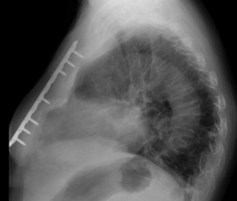

Μετεγχειρητική εικόνα επιδιόρθωσης κατάγματος στέρνου (Ευγενική παραχώρηση Dr. V. Penopoulos)